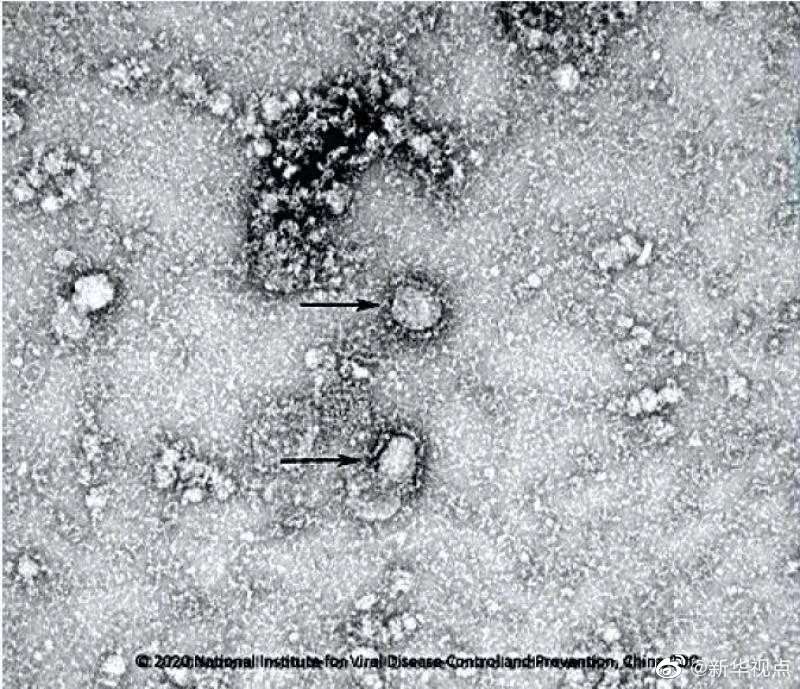

好消息!中國疾控中心成功分離我國首株新型冠狀病毒毒種,它長這樣!

國家病原微生物資源庫于2020年1月24日發布了由中國疾病預防控制中心病毒病預防控制所成功分離的我國第一株病毒毒種信息及其電鏡照片、新型冠狀病毒核酸檢測引物和探針序列等國內首次發布的重要權威信息,并提供共享服務??床《尽罢嫒荨薄ㄓ浾咛飼院?、王秉陽)